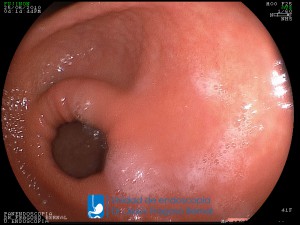

La Unidad de Endoscopía fue creada en 2002 por el Dr. Jesús Fragoso Bernal, es pionera en el estado por la utilización de la tecnología más avanzada, que nos permite ofrecer servicios integrales de diagnóstico y tratamiento para las enfermedades del aparato digestivo.